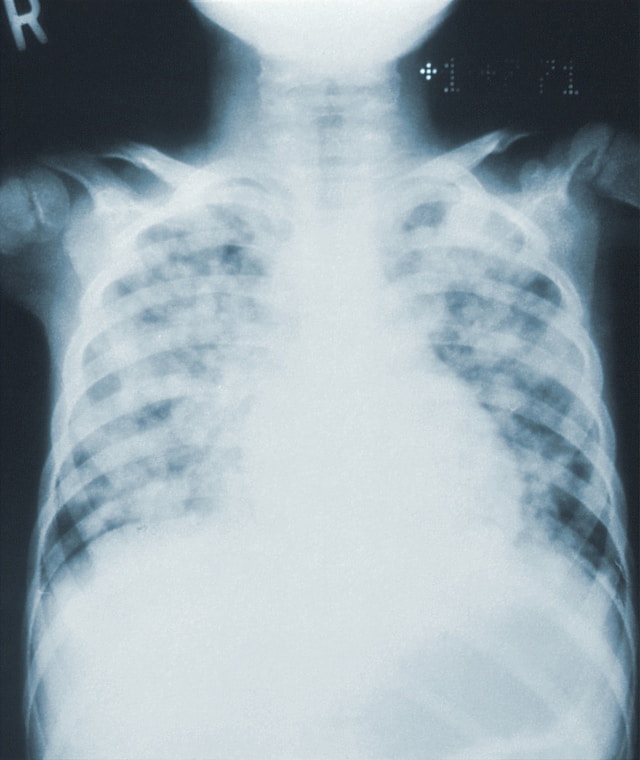

폐렴 증상

폐렴은 한쪽 또는 양쪽 폐의 기낭에 염증을 일으켜 공기주머니에 체액이나 고름이 차는 감염입니다. 폐렴의 증상은 감염 원인, 질병의 중증도, 개인의 연령 및 전반적인 건강 상태에 따라 다를 수 있지만 다음을 포함할 수 있습니다. 첫 번째, 기침입니다. 이것은 마른기침이거나 가래나 점액을 생성하는 생산적인 기침일 수 있습니다. 두 번째 고열 38도는 폐렴에 취약합니다. 세 번째, 숨 가쁨입니다. 운동을 하거나 쉬고 있을 때 발생할 수 있으며 경증에서 중증까지 다양합니다. 네 번째, 흉통입니다. 심호흡이나 기침으로 약화되는 예리하거나 둔한 통증 일 수 있습니다. 다섯 번째, 피로와 발한입니다. 매우 피곤하거나 허약한 느낌으로 특히 밤에 땀을 많이 흘리는 것은 일반적인 증상입니다. 여섯 번째, 오한입니다. 열과 함께 추위와 떨림이 발생할 수 있습니다. 그리고 메스꺼움과 구토 같은 증상은 폐렴이 심할 경우 나타날 수 있습니다.